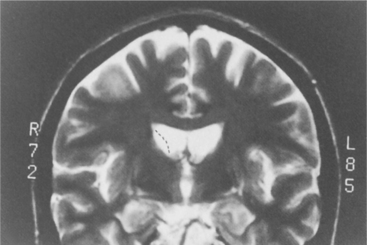

Although the cause remains unknown, pathologic findings show a consistent pattern of tissue changes in the brain. The ventricles are enlarged as a result of atrophy of the adjacent basal ganglia, specifically the caudate nucleus and putamen (collectively the striatum) (Fig. 31-5). This is due to extensive loss of small and medium-sized neurons. The volume of the brain can decrease by as much as 20%. Caudate atrophy correlates with a measured decline in Mini-Mental State Examination scores but not with the severity or duration of neurologic symptoms. It is the atrophy of the putamen that correlates with neurologic symptoms. The atrophy of the cortices appears to occur at the same rate as that of the striatum. White matter degeneration in the frontal cortex appears to be associated with the course of the disease. Slower disease progression appears to be correlated with more white matter changes. The more aggressive progressive disease is related to less white matter and more striatal damage. Other subtle changes occur in the cortex and cerebellum, including both loss of neurons and production of glial cells that inhibit neural transmission.70

Figure 31-5 Atrophy seen in the caudate and putamen in a person with Huntington’s disease. As the disease progresses there is a change in the caudate at the interface with the ventricle. The outline becomes more and more concave, representing the progressive atrophy.